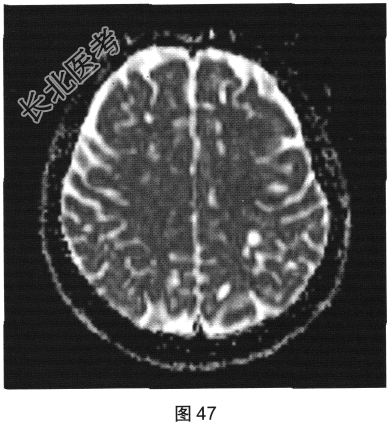

- 多项选择题2.[提示]患者行FLAIR、DWI及增强扫描,见图45~图54。该患者MRI影像的主要阳性表现有( )

C、双侧放射冠及半卵圆中心多发条状、圆形及卵圆形异常信号灶

E、病灶呈长T1、长T2信号,FLAIR为低信号,DWI为低信号,ADC为高信号